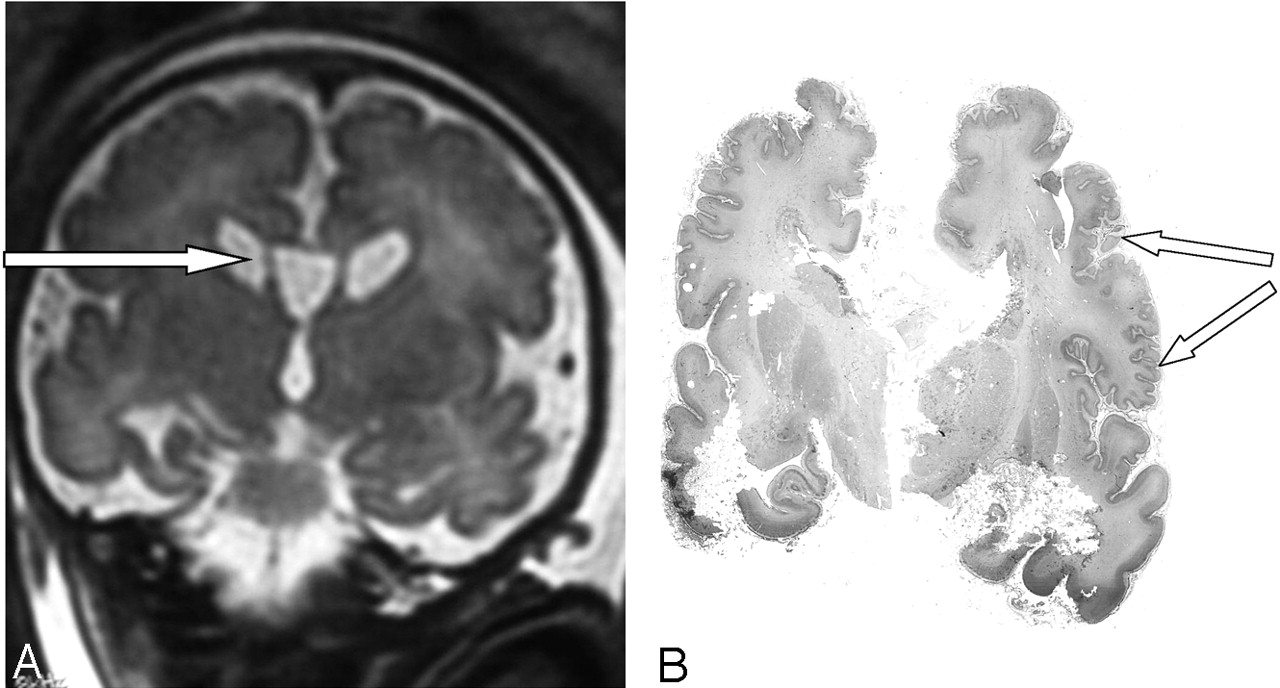

Case 2. Coronal T2-weighted MR image shows large cavum and bilateral subependymal pseudocysts (A). Postmortem coronal section confirms the micropolygyric pattern predominating in the frontal and perisylvian cortex (B).

The parents elected to terminate the pregnancy at 36 weeks. Postmortem examination of the male fetus showed moderate growth retardation with weight at the tenth percentile. The fetus presented dysmorphic features, hepatosplenomegaly, renal cortical microcysts, small adrenals, and multiple calcific stippling of the patellae. Macroscopic examination of the brain revealed moderate ventricular enlargement with large cavum, thin corpus callosum, and small germinolytic cysts. Histopathologic analysis revealed microgyria predominating in the frontal and perisylvian areas (Fig 3). Abnormal gyration patterns were also observed in the inferior olivary nucleus and in the dentate nucleus of the cerebellum, which presented with diffuse heterotopias. ZS was confirmed by a marked elevation of the VLCFA in the amniotic fluid.